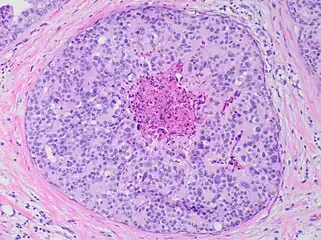

80% of cases in the United States are detected by mammography screening.[24] More definitive diagnosis is made by breast biopsy for histopathology.

It is classified according to the architectural pattern of the cells (solid, cribriform, papillary, and micropapillary), tumor grade (high, intermediate, and low grade), the presence or absence of comedo histology,[16] or the cell type forming the lesion in the case of the apocrine cell-based in situ carcinoma, apocrine ductal carcinoma in situ.[25]